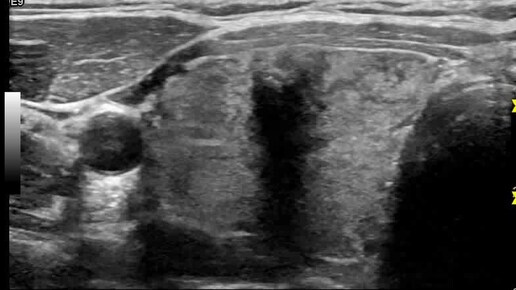

Видео к статье "Стратификация узлов щитовидной железы. TI-RADS-4" https://dzen.ru/a/ZwNx-uQp-Sfk6L46

Ультразвуковые находки от врача УЗД Зорина Я.П.